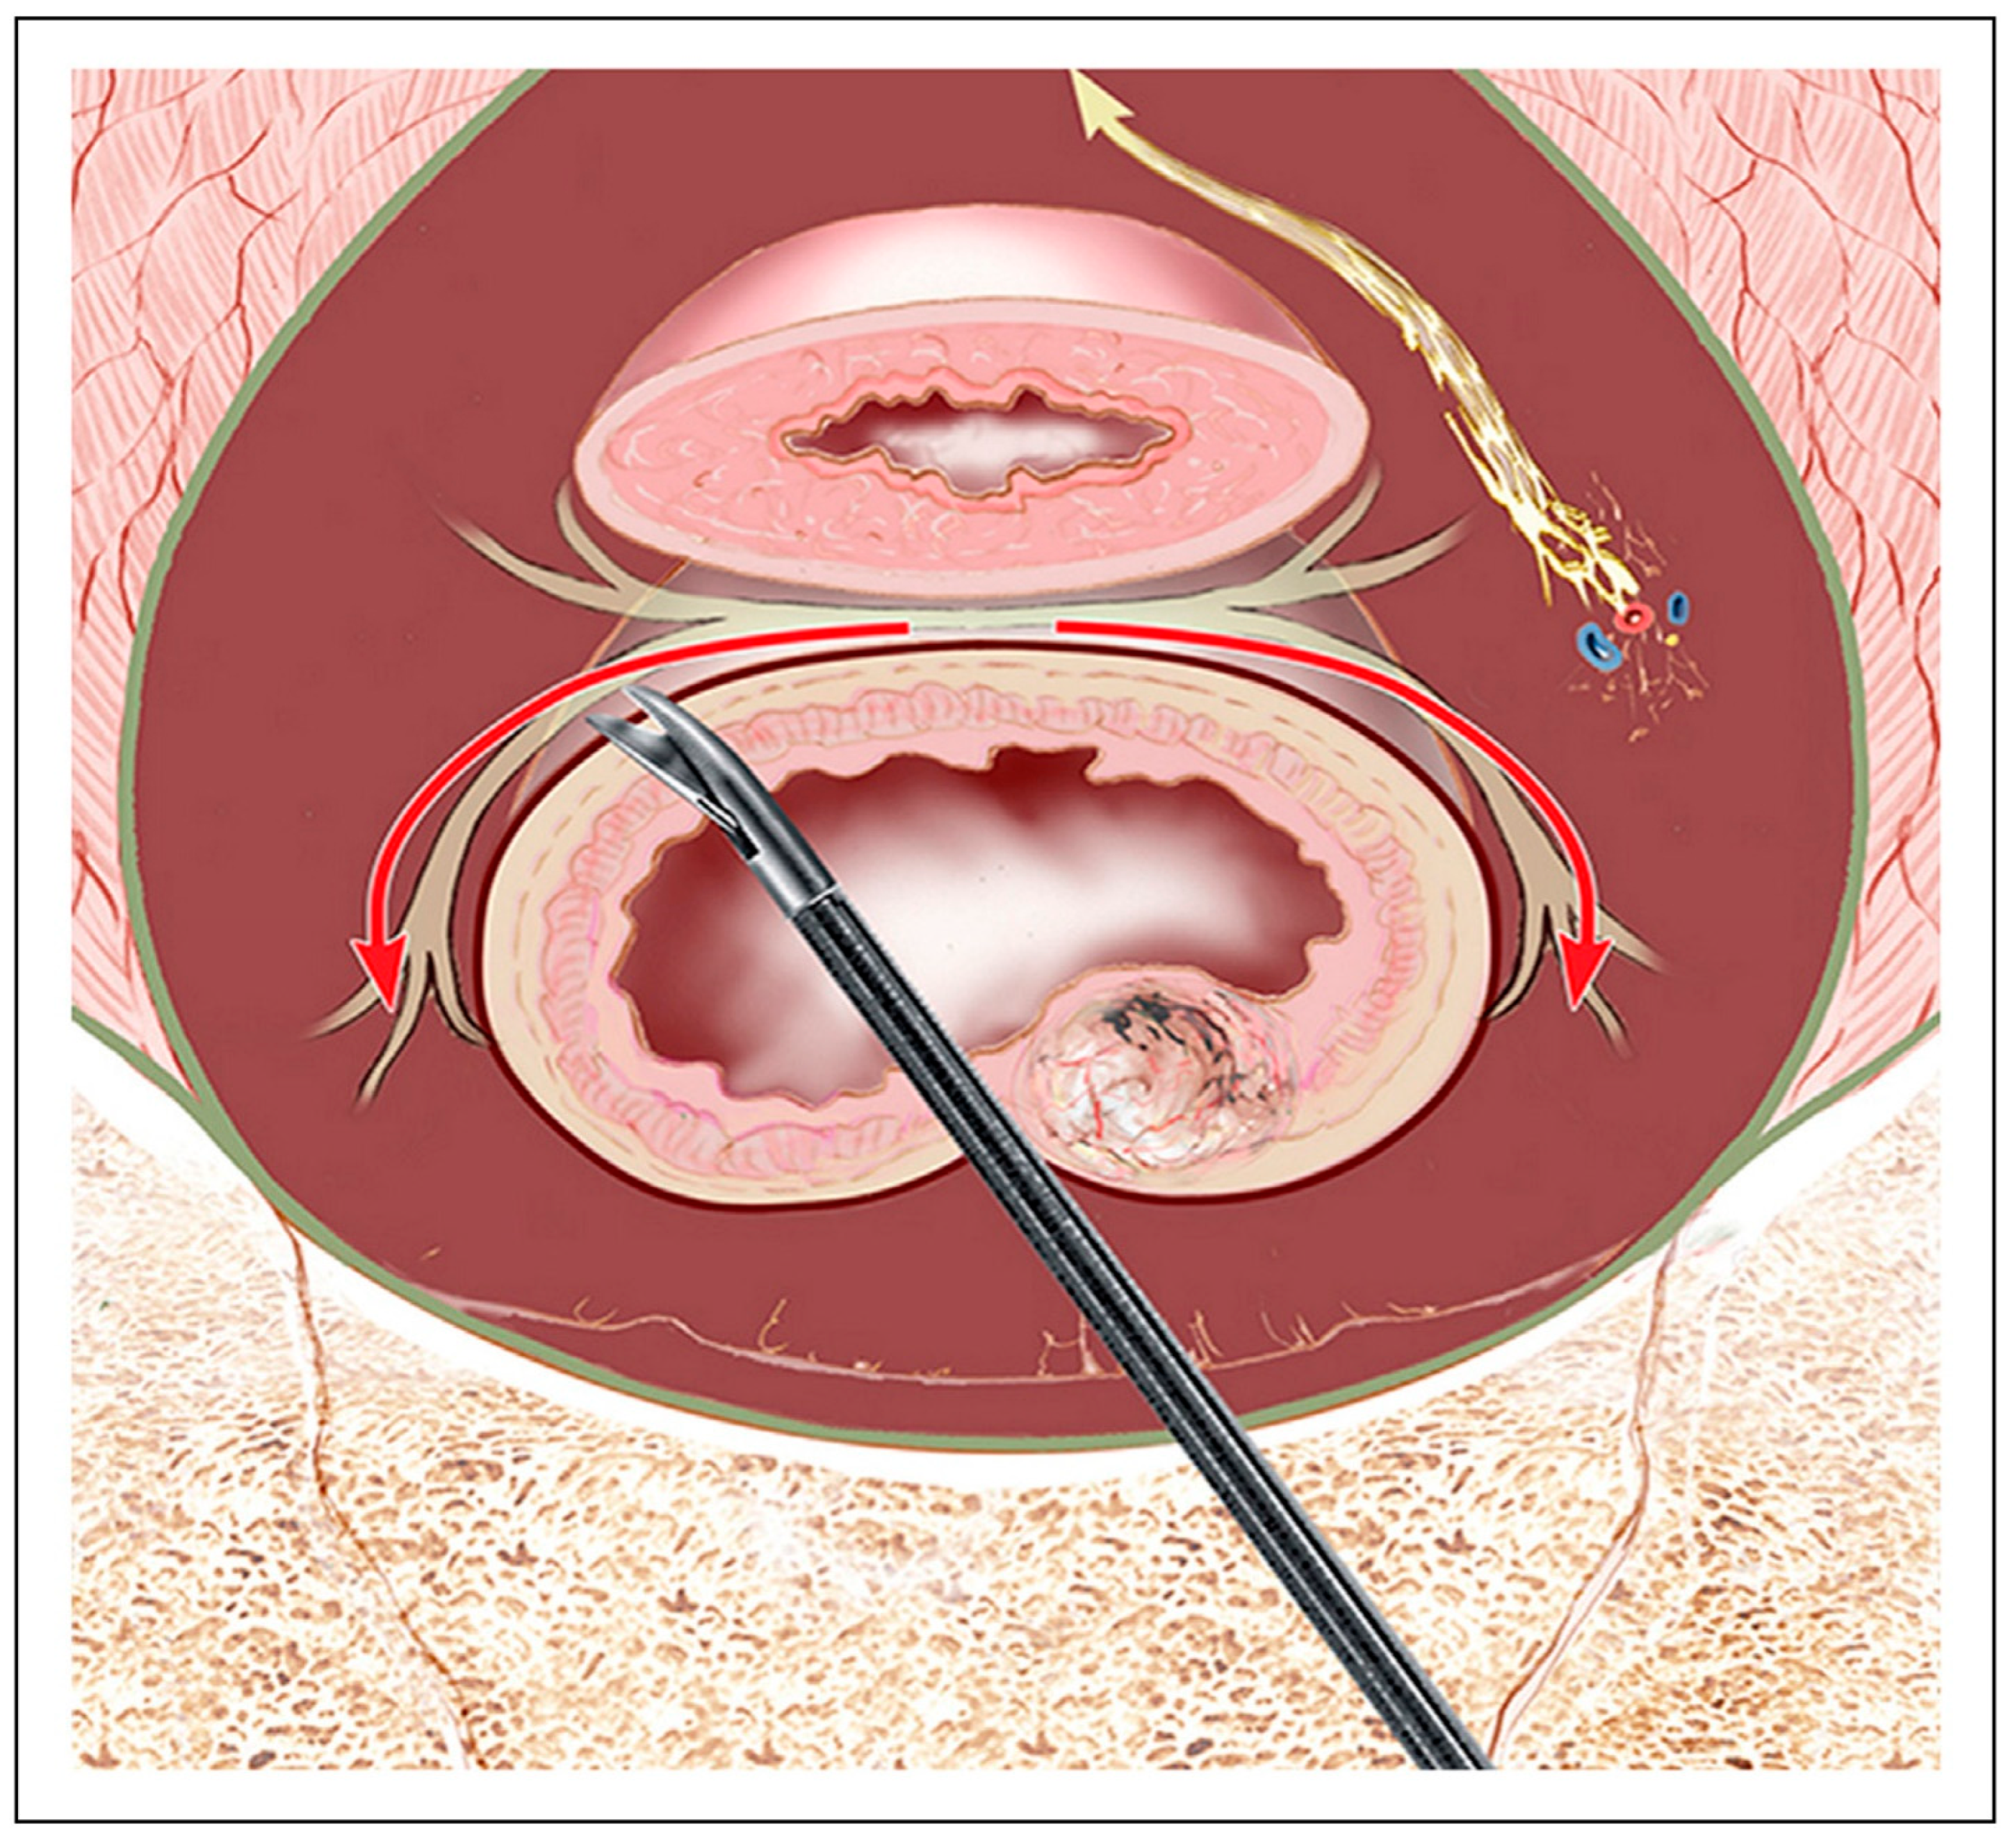

| Near-Infrared Fluorescence (NIR) | Uses ICG or targeted agents for real-time visualization | Improves intraoperative nerve visibility | [41,53] |

- Jin, H.; Zheng, L.; Lu, L.; Cui, M. Near-infrared intraoperative imaging of pelvic autonomic nerves: A pilot study. Surg. Endosc. 2022, 36, 2349–2356. [Google Scholar] [CrossRef] [PubMed]